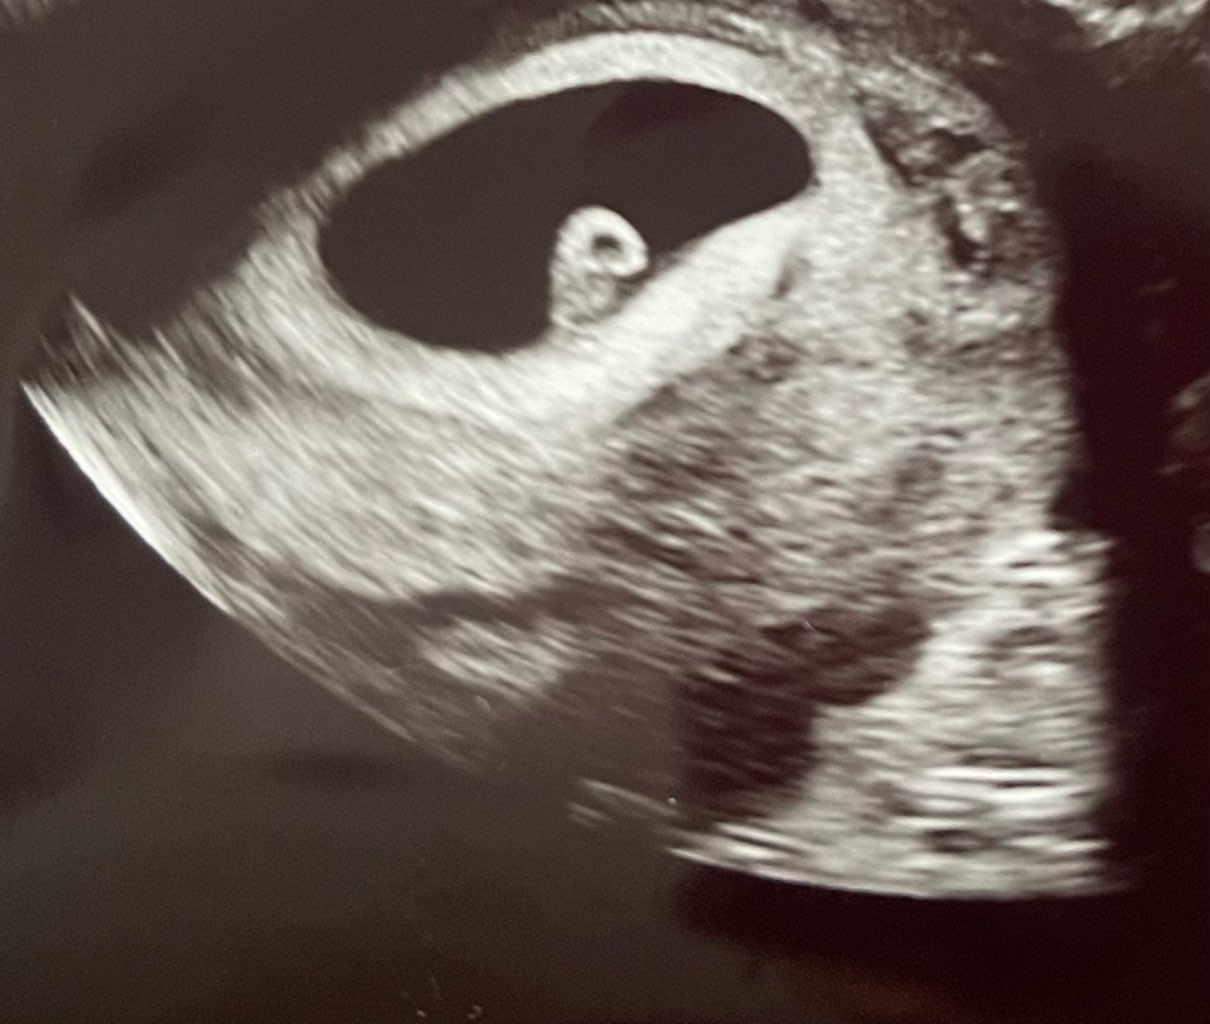

po miesiącu -8kg było. Mam nadzieje na druga córcię

bo z synem zorientowałam się dopiero jak odrzuciło mnie od kawy i jak zwymiotowałam zaraz po zjedzonej z apetytem mandarynce.